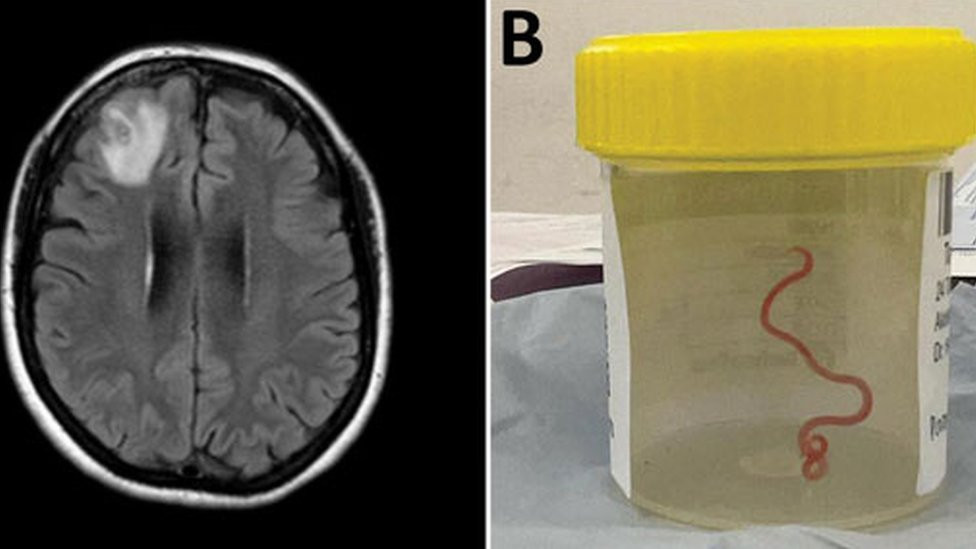

ANUSkenirani prikaz mozga i parazit u posudi za uzorke Iz mozga žene u Australiji, lekari su tokom operacije izvukli živog crva, dugog osam centimetara, što je prvi takav slučaj u svetu. „Struktura poput strune“ izvučena je iz oštećenog tkiva prednjeg dela glave engleskog pacijenta tokom operacije u Kanberi, jednom od većih australijskih gradova prošle godine. […]

Iz mozga žene u Australiji, lekari su tokom operacije izvukli živog crva, dugog osam centimetara, što je prvi takav slučaj u svetu.

„Struktura poput strune“ izvučena je iz oštećenog tkiva prednjeg dela glave engleskog pacijenta tokom operacije u Kanberi, jednom od većih australijskih gradova prošle godine. Crveni parazit je, prepostavlja se, moguće bio u mozgu ove žene do dva meseca.

„Svako ko je prisustvovao operaciji se šokirao kada je hirurg pincetom izvukao vijugav, strani organizam, dug osam centimetara, crvene boje.

Skeniranjem joj je otkriveno „atipično oštećenje u desnom prednjem delu mozga“.

Biopsijom u junu 2022. godine saznali su i uzrok njenog stanja.